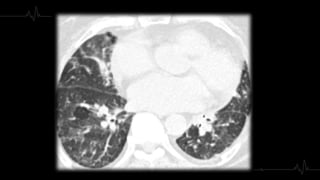

3. Extensión

4. AFECTACIÓN

PARENQUIMATOS

A● Inicialmente: Opacidad en vidrio

deslustrado, segmentaria, de morfología

triangular y base pleural.

● Con el paso del tiempo: Consolidación.

● Se puede identificar una atelectasia del

área afecta, la isquemia pulmonar provoca

una alteración del surfactante con colapso

secundario.

4. AFECTACIÓN PARENQUIMATOS A● Inicialmente:Opacidad en vidrio deslustrado, segmentaria, de morfología triangular y base pleural. ● Con el paso del tiempo: Consolidación. ● Se puede identificar una atelectasia del área afecta, la isquemia pulmonar provoca una alteración del surfactante con colapso secundario.